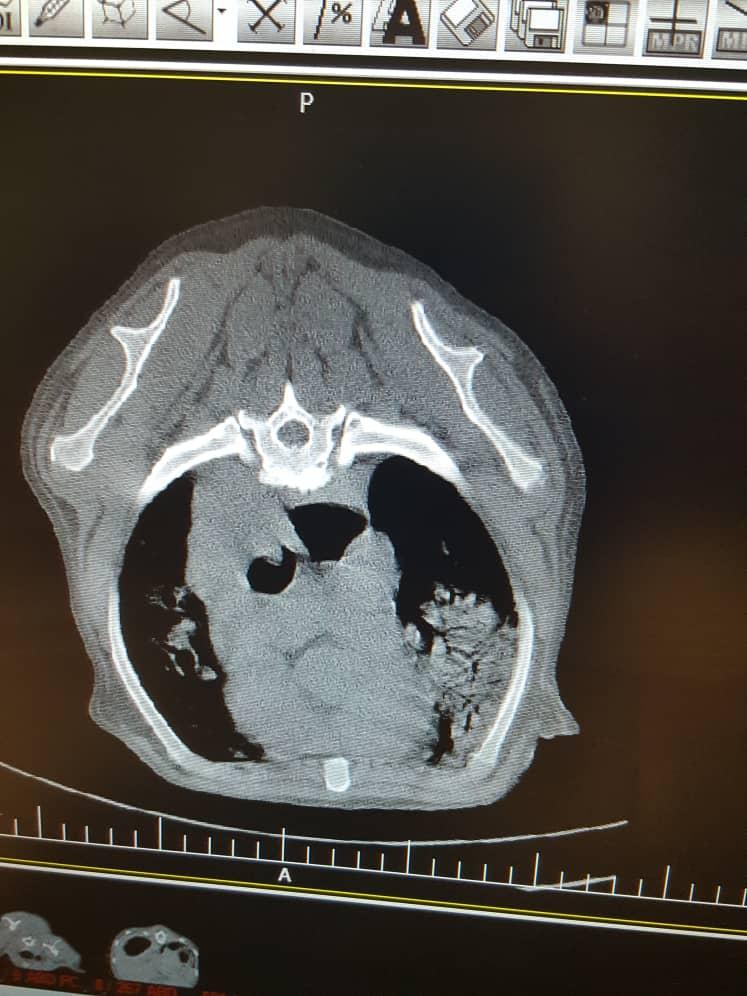

I have a 10 yo AKC registered labrador who currently lives in overseas. He has developed severe dysphagia, barrium swallow showed obstruction and CT scan showed large lung tumor. His Vet in overseas says nothing can be done for him. But I want a second opinion from a vet in US please look at the CT and let me know. I only can send 3 images here. But I have more. Thanks

The problem is that you can possibly try to remove the tumors with surgery. However, your dog is an old dog and the anesthetic risk in a dog with a large lung tumor at this age is great and it is likely that your dog will die during anesthesia. The obstruction can probably be removed, but again the anesthetic risk is great. Recuperation will also be extensive and there is a big chance that your dog's tumors will reoccur before he has even returned to wellbeing from the surgery, should he have survived it. I agree with the veterinarian who diagnosed him (considering what you have reported). You can get a second opinion from an oncologist overseas. They are no worse than the ones here in the US. I am sorry your dog is so ill.